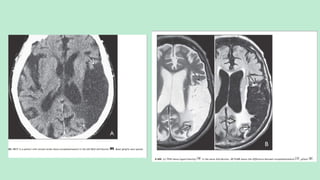

FOGGING PHENOMENON

Transient return of the infarcted cortex to a near normal appearance in the

evolution of stroke is called the Fogging Phenomenon.

Occurs in about 50% cases between (2-3 weeks).

Causes:

1. Lipid laden macrophages migration.

2. Proliferation of capillaries.

3. Reduced edema and

4. Cortical laminar necrosis.

CECT will show vivid ribbon like cortical enhancement.